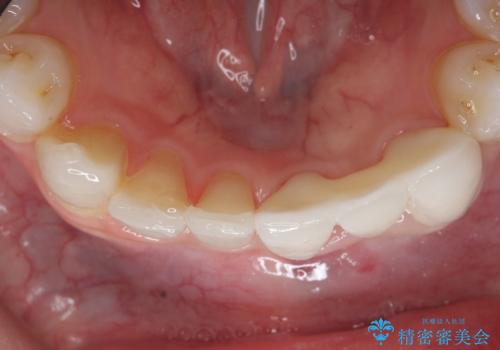

左下123番のブリッジになるが、左下1番と3番の歯軸が合っておらず神経治療が必要になる可能性があるため部分矯正を提案したところ、希望されなかったため、そのままの歯軸でオールセラミッククラウンによる補綴を行いました。

今回用いたオールセラミッククラウンはジルコニアフレームという白い素材の上にセラミックを盛っているため、審美性が非常に高いのが特徴です。

また、ジルコニアは人工ダイヤモンドの材料にも使われているほど高い強度を持っており、そのためオールセラミッククラウンは審美性だけでなく、奥歯やブリッジの補綴も可能とするクラウンです。